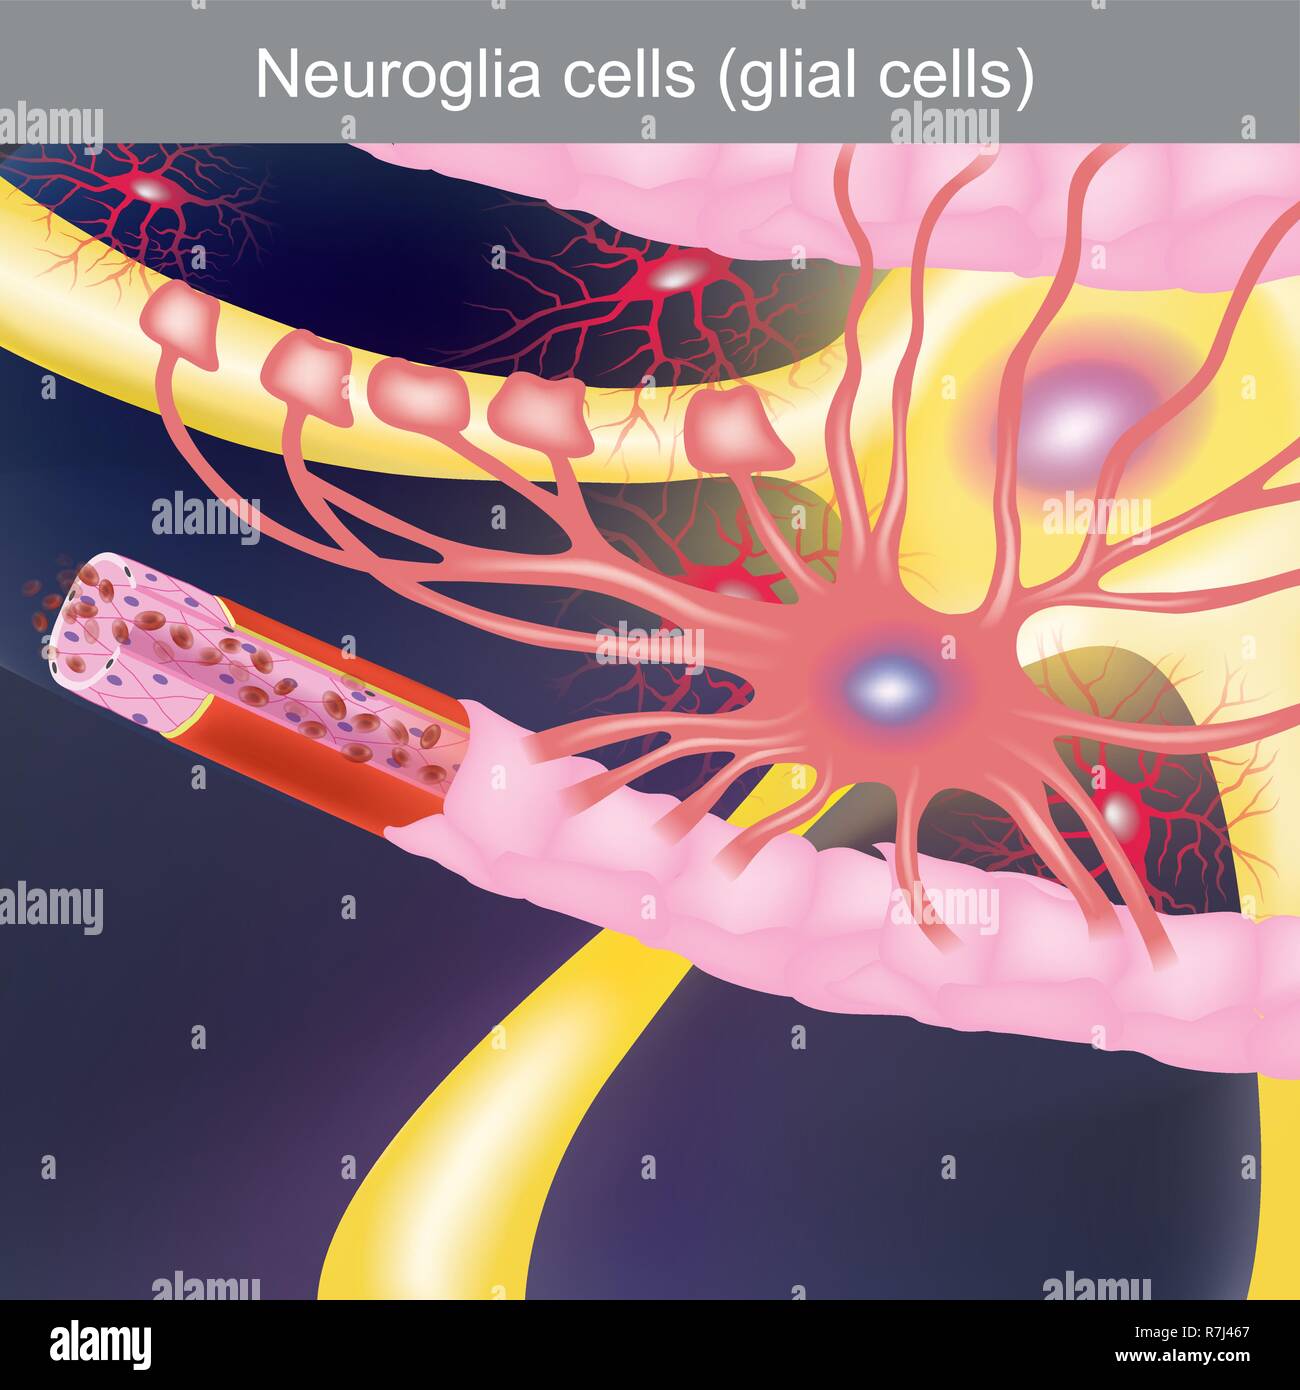

Il dovere è quello di curare il sistema nervoso centrale, per portare cibo e ossigeno alle cellule nervose. Illustrazione Vettorialehttps://www.alamy.it/image-license-details/?v=1https://www.alamy.it/il-dovere-e-quello-di-curare-il-sistema-nervoso-centrale-per-portare-cibo-e-ossigeno-alle-cellule-nervose-image228435823.html

Il dovere è quello di curare il sistema nervoso centrale, per portare cibo e ossigeno alle cellule nervose. Illustrazione Vettorialehttps://www.alamy.it/image-license-details/?v=1https://www.alamy.it/il-dovere-e-quello-di-curare-il-sistema-nervoso-centrale-per-portare-cibo-e-ossigeno-alle-cellule-nervose-image228435823.htmlRFR7J467–Il dovere è quello di curare il sistema nervoso centrale, per portare cibo e ossigeno alle cellule nervose.